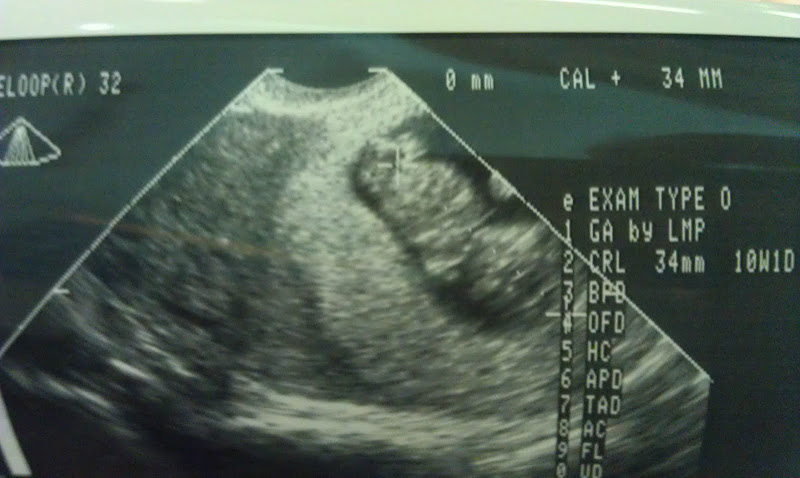

That’s right!! I’m pregnant! And here’s the REAL feet: